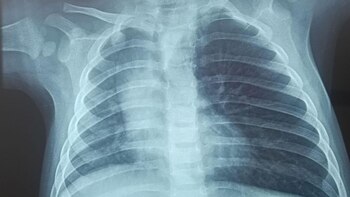

En el establecimiento, los médicos identificaron que la menor tenía un cuerpo extraño alojado en su vía aérea, específicamente en el pulmón derecho, lo que le provocaba insuficiencia respiratoria severa.

Ante la gravedad de la situación, los médicos del Hospital Regional del Cusco decidieron intervenir el domingo. Sin embargo, la menor sufrió un paro cardiorrespiratorio durante el procedimiento, lo que complicó aún más su delicado estado de salud. A pesar de la falta de instrumental pediátrico especializado, el equipo médico logró estabilizarla a través de ventilación mecánica.

La operación, que duró más de una hora y media, fue un éxito, y los especialistas lograron retirar el tarwi seco de la vía respiratoria de la pequeña. Su evolución, según el equipo médico, ha sido favorable, y actualmente se encuentra bajo observación en el Hospital Regional del Cusco.